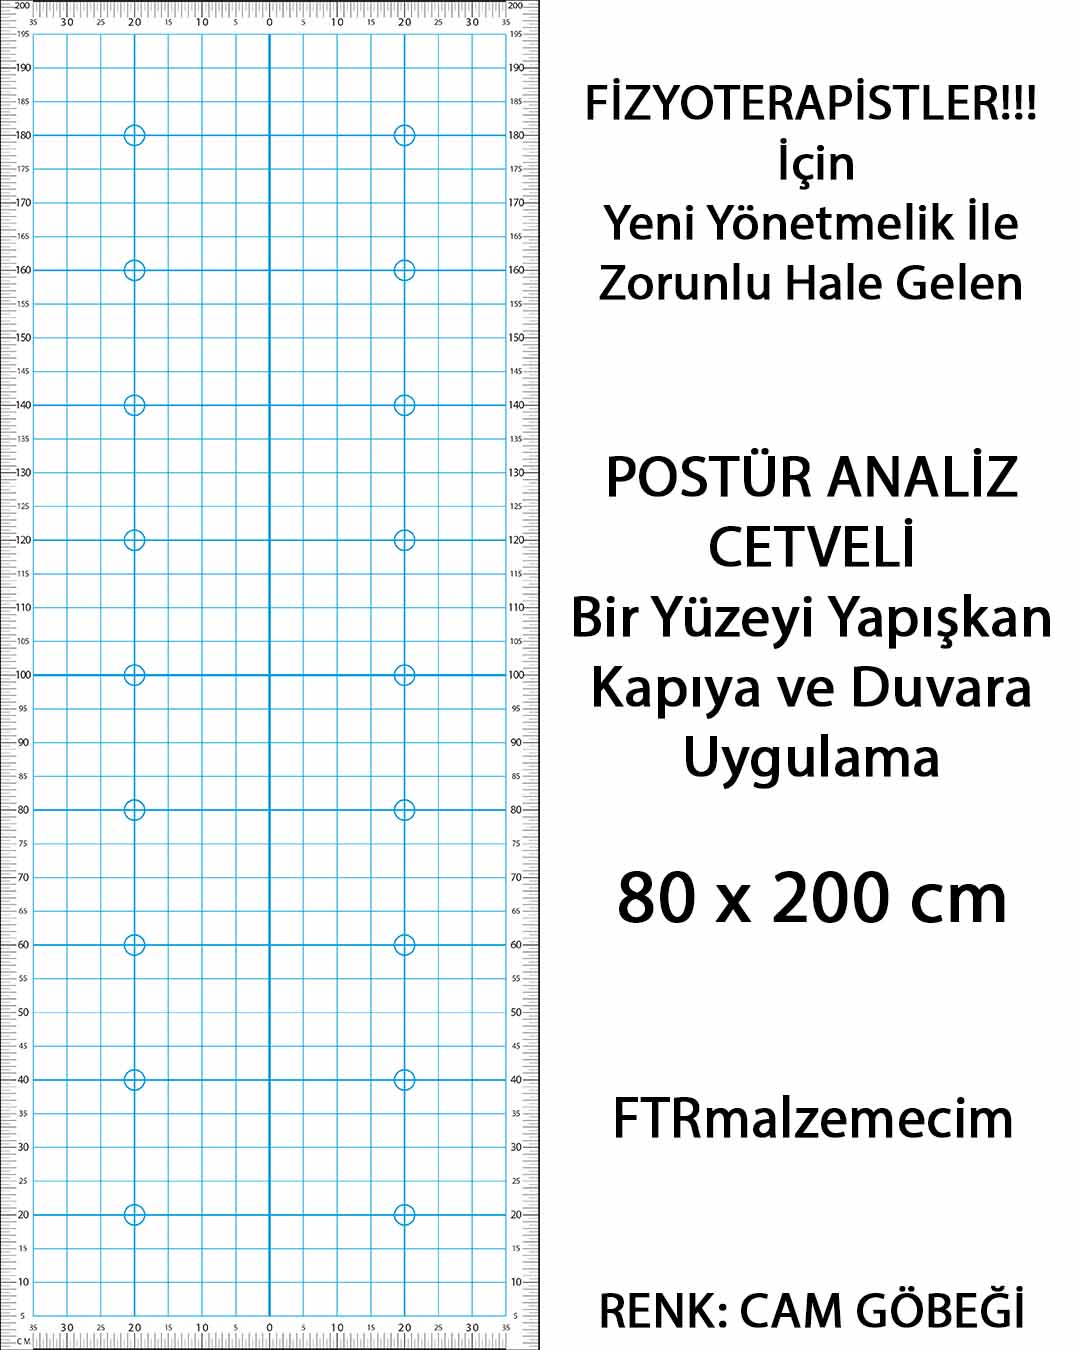

Ftrmalzemecim.com’da; egzersiz ekipmanlarından elektroterapi cihazlarına, sıcak-soğuk uygulama ürünlerinden yürüteç, baston ve tekerlekli sandalye gibi yardımcı ekipmanlara kadar geniş bir ürün yelpazesi bulunmaktadır. Ürünlerimiz, uzman fizyoterapistler tarafından test edilmekte ve klinik kullanıma uygunluğu onaylanarak satışa sunulmaktadır. Her biri Sağlık Bakanlığı onaylı, kaliteli ve güvenilir ürünlerdir.

Yeni bir fizik tedavi merkezi kurmayı planlayan fizyoterapistlere A’dan Z’ye klinik kurulum danışmanlığı sunmaktayız. Gerekli ekipman listesinin oluşturulmasından yönetmeliklere uygun ürün seçimine kadar tüm süreçlerde profesyonel destek sağlıyoruz. Güncel mevzuatı yakından takip eden uzman kadromuzla, sadece ürün değil, bilgi ve çözüm de sunuyoruz.